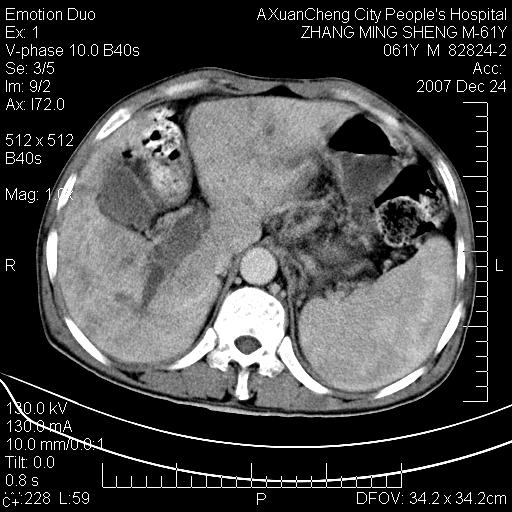

标题: CT11031:M61Y,胰腺占位

大家侃侃门静脉和胆管系统怎么回事,肝内转移?

胰腺癌肝转移

肝硬化,门脉高压,脾肿大;弥漫性肝癌,肝内、门脉、腹膜后淋巴结转移,肝内外胆管扩张,胰头区占位,建议mr检查

胰腺癌伴肝内转移;门脉、肠系膜上v癌栓形成。

考虑为:胰腺癌伴肝脏转移、腹膜后淋巴结转移,门静脉及肠系膜上静脉瘤栓形成。

胰体尾癌伴肝内转移,门静脉及肠系膜上静脉瘤栓形成.